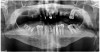

Figure 2: These re-operative panoramic radiograph.

Figure 2

This prosthetically driven workflow can be completed in two patient appointments. Following acceptance of the treatment plan, the process begins with a digital denture design. Either conventional or digital impressions and jaw relation records are made. Any conventional records are sent to the laboratory to fabricate models for scanning. At the first appointment, there is also a comprehensive esthetic evaluation (Figure 1) that will assist in determining the desired tooth position for the future prosthesis. This includes determining the appropriate midline, incisal edge position, lip support, plane of occlusion, vertical dimension, and tooth and gingiva colors. Lastly, a CT scan of the patient is acquired (Figure 2).